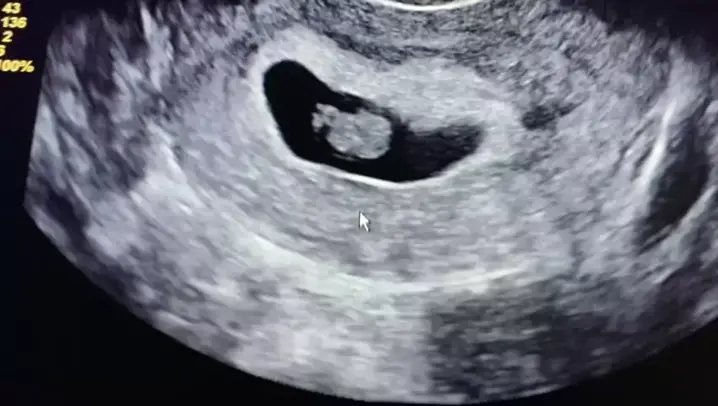

nossa primeira ultrassom 🤰 kkkk